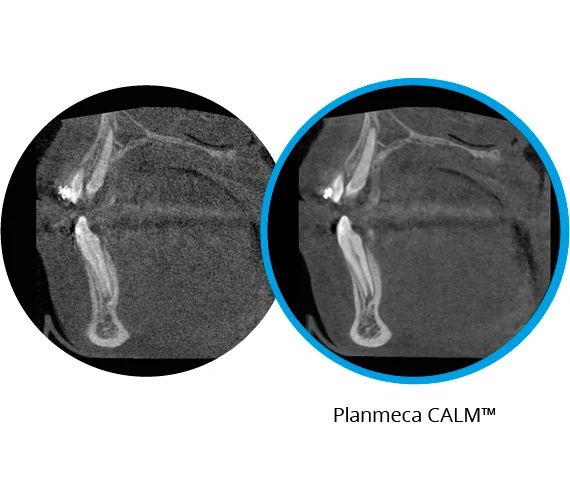

Алгоритм коррекции артефактов движения

Planmeca CALM® — это инновационный способ удаления артефактов, вызванных движением пациента, на снимке КЛКТ. Алгоритм предлагается в качестве опции для всех аппаратов Planmeca 3D.